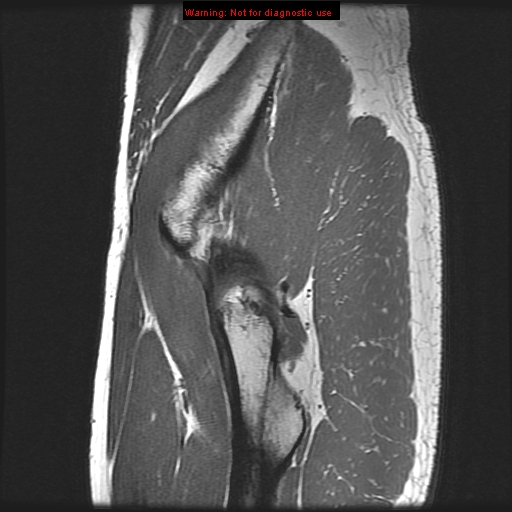

Stanford MSK MRI Atlas

psoas muscle gluteus minimus muscle

obturator internus muscle acetabular labrum